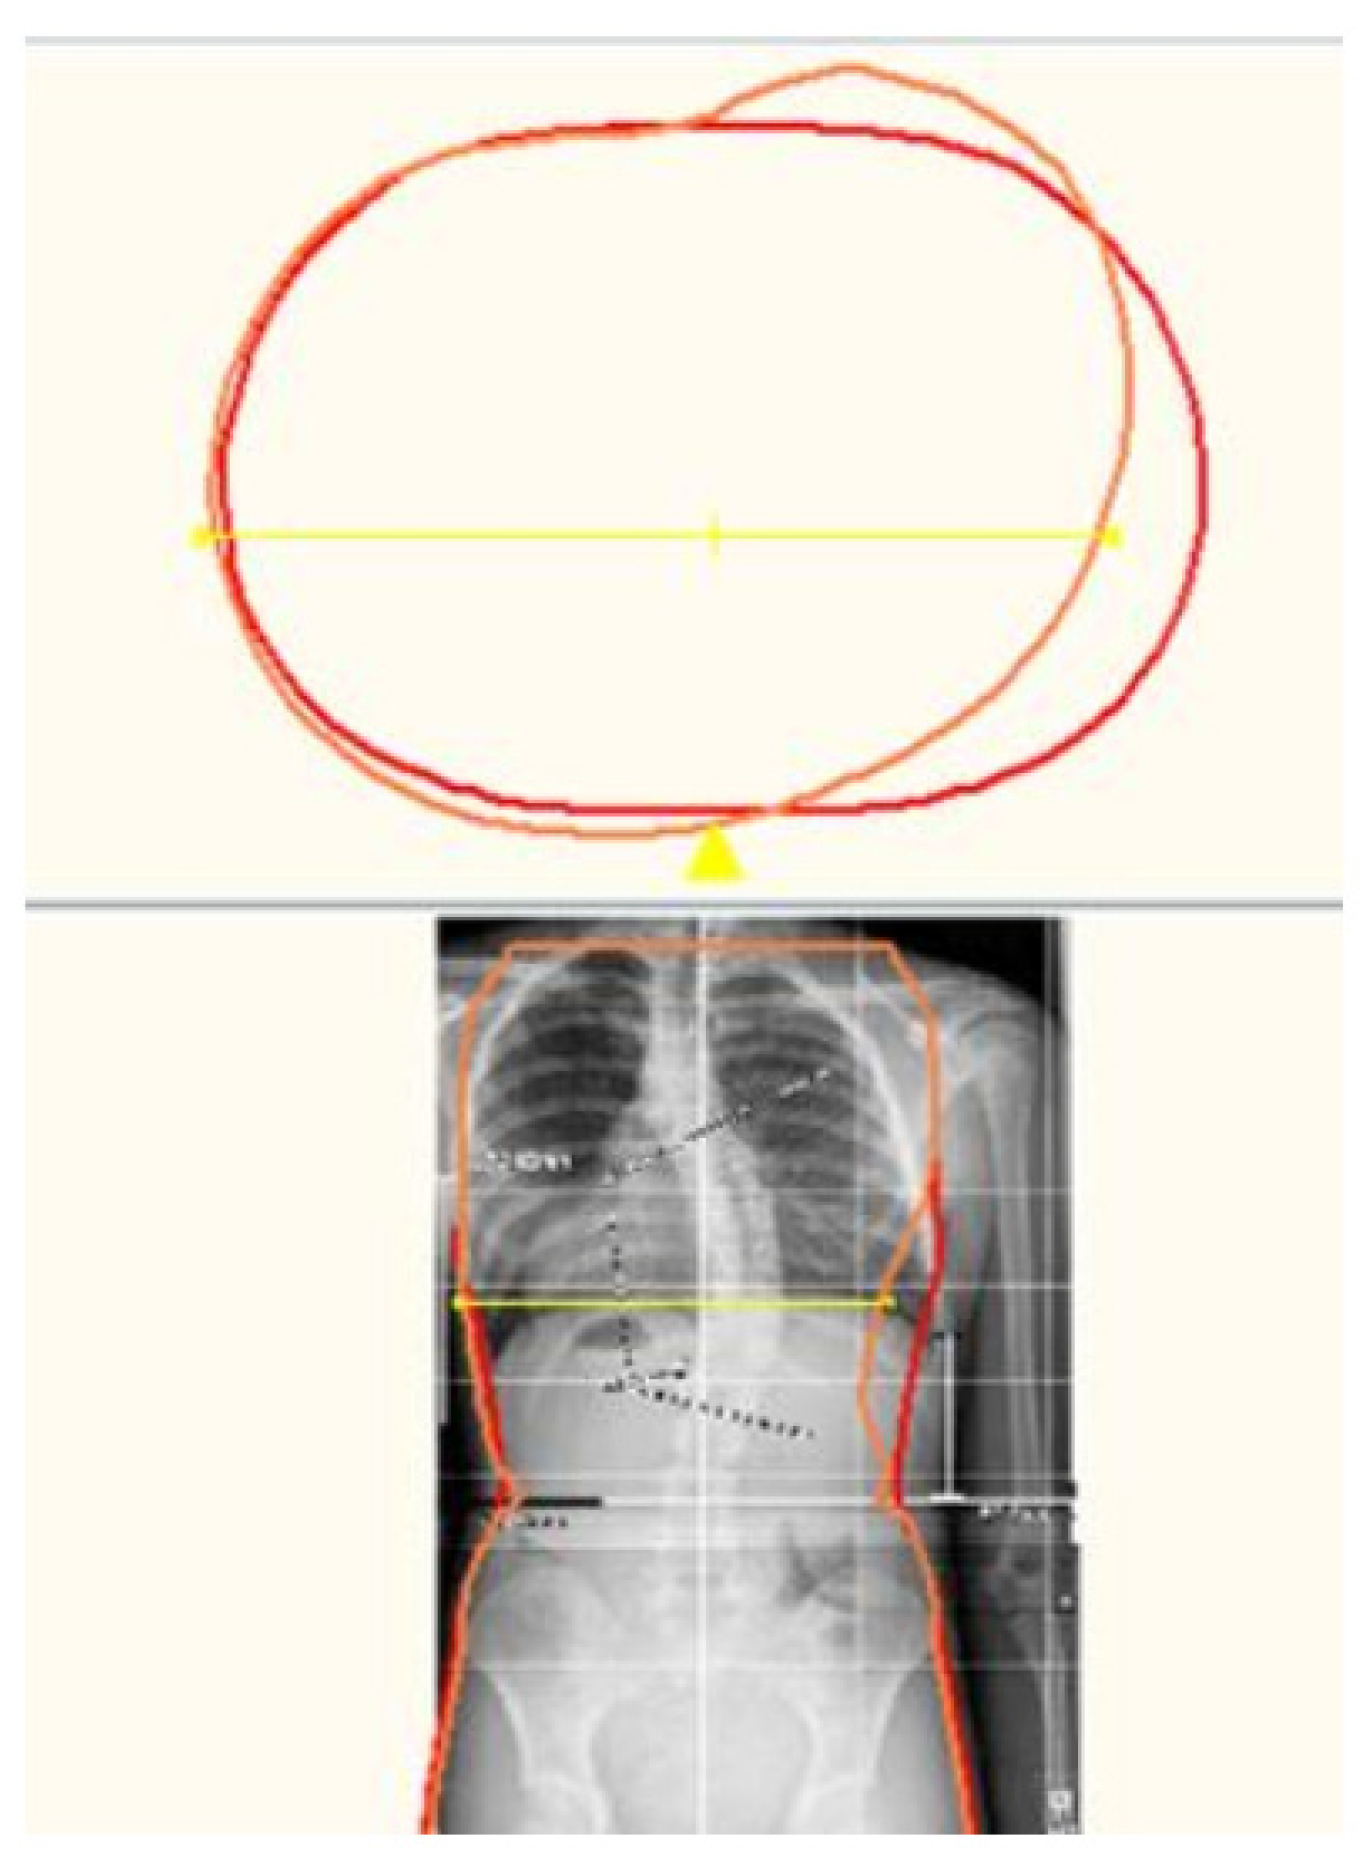

The scan is then modified according to the Boston Brace 3D principles, which include internal pushes and shifts opposite to the areas of reliefs, the dimensions of which are determined by clinical exam and X-ray blueprint. The internal forces are oriented to provide an anterior/medially resultant vector while maintaining the individual’s overall sagittal balance. Figure 5 shows a before-and-after modification model of a patient. Figure 6 provides a top-down transverse plane view through the apex of a right thoracic curve and shows the internal shift and push applied with the opposing area of relief. This modification process results in an asymmetrical model of the patient over which the brace is fabricated.

Figure 5. Modified scan for a Boston Brace 3D orthosis.

Figure 6. Transverse view through apex.